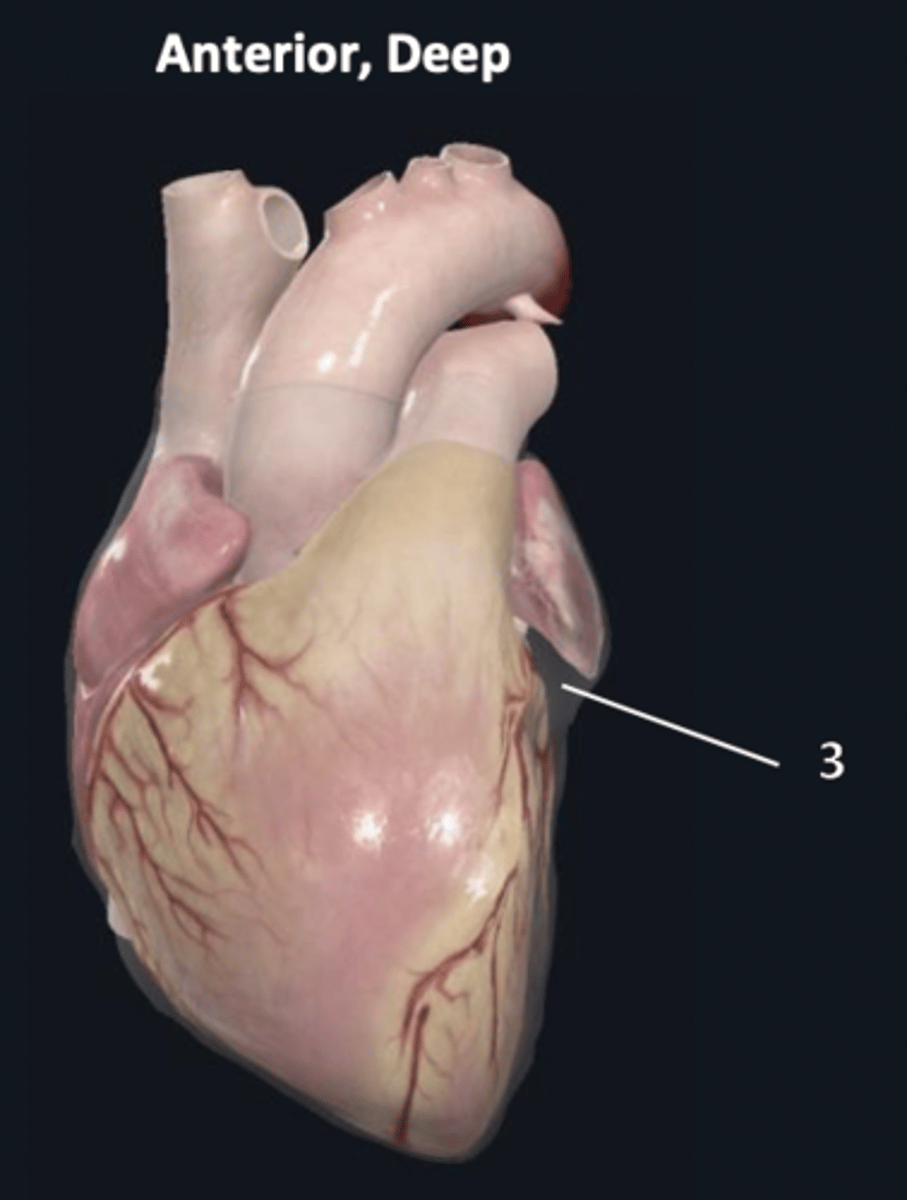

visceral layer

3 (deep to 2 other layers)

diaphragmatic surface

3

sternocostal surface

4

atrioventricular groove

5

anterior interventricular sulcus

6

posterior interventricular sulcus

7